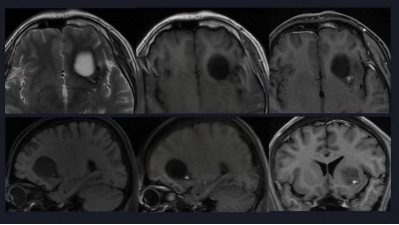

同心圆硬化,又称Balo's concentric sclerosis(BCS),主要侵袭大脑的白质区域,而小脑、脑干、脊髓则相对较少受累。其病理生理机制尚未完全明确,但多数研究认为它与多发性硬化有着千丝万缕的联系,可能是其一种特殊的变异形态。

同心圆硬化的临床表现多样,无特异性。它常以急性或亚急性发病,好发于青壮年,男女比例在国内外报道中略有差异。患者可能出现各种脑部症状和体征,如精神障碍、头痛、失语、偏瘫、认知或行为异常和癫痫发作等。这些症状的出现,无疑给患者的生活带来了极大的困扰。